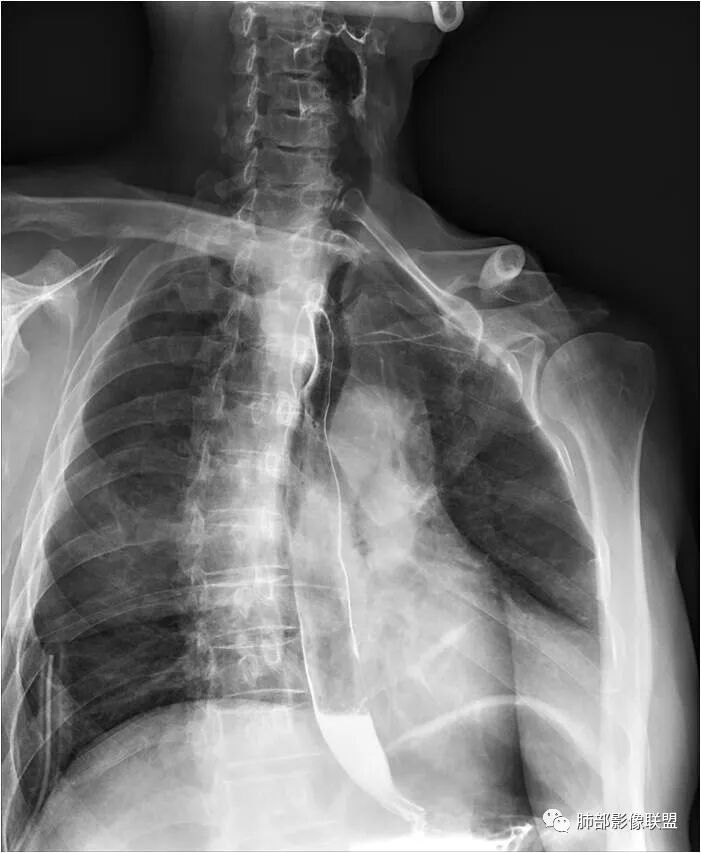

晨读:男性,体检发现右后纵隔占位,CT示右后纵隔梭形软组织肿块,局部与食管壁分界不清,压迫气管与食管,平扫密度均匀,增强轻度不均匀渐进性强化,内部可见片状低密度区,考虑为1、食管来源平滑肌瘤。2、神经鞘瘤

2.定位:右后上纵隔肿块,与食管关系密切,边缘光滑,冠状位显示肿块与食管壁结构相顺延,上下径大于横径,呈现跨管壁内外生长倾向,食管管腔狭窄,而气管腔内未见突入,因此食管来源肿块可能大。

3.结合CT增强图像及食道钡餐影像(管壁整体柔软,粘膜线完整),提示肿块来源于粘膜下。

肿块影边界清楚、局限,未见管壁及周边浸润,提示良性病灶。

4.肿块渐进性强化,局部可见低强化区(下图红箭头所示),可以符合神经鞘瘤AB区的影像特点,尽管该部位神经鞘瘤罕见,毕竟食管壁也是有神经走行的,解剖也提示诊断的方向。

须排除的是平滑肌瘤及间质瘤。血管瘤及囊肿因强化方式不支持。